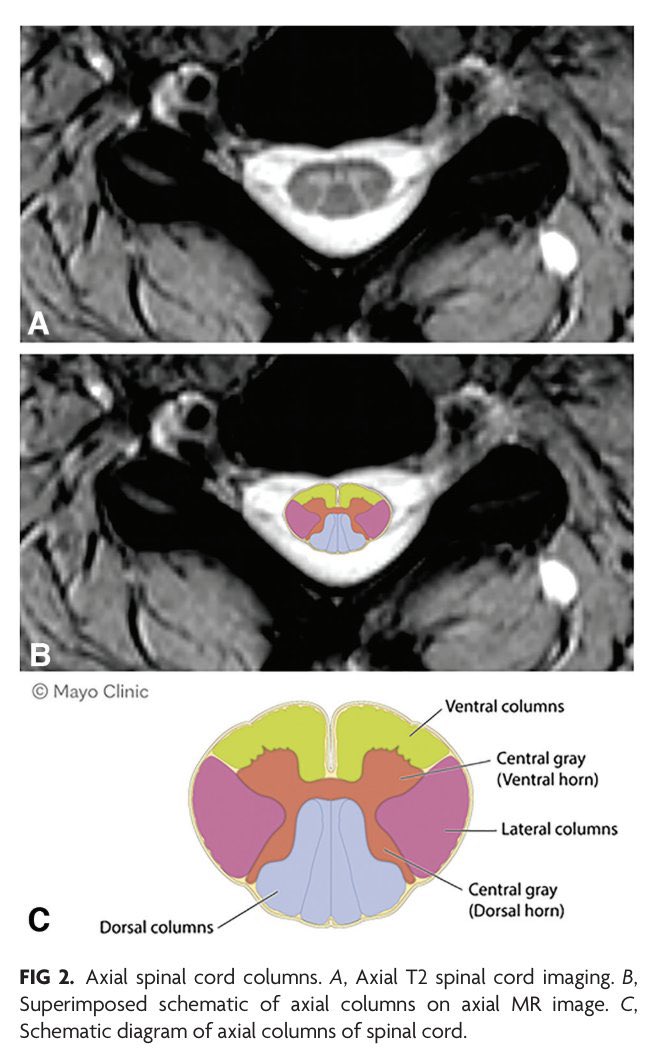

When the sagittal view don’t show us how severe is the stenosis. It’s necessary to evaluate the axial view that is indispensable for an accurate and complete diagnosis of conditions affecting the lumbar spine, providing crucial information that complements sagittal and coronal